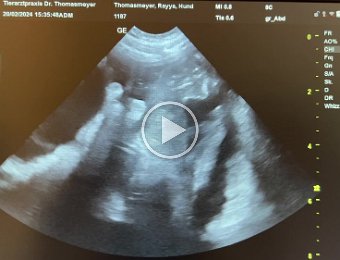

36. Tag

20-24.02.24